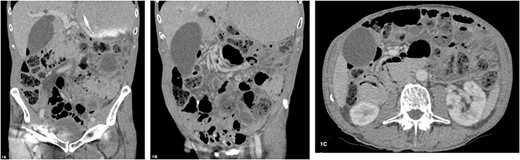

An 84-year-old male with untreated primary SjS was referred to the emergency department with acute abdominal pain, distension and vomiting. He presents on the background of oesophageal dysmotility, sinus bradycardia and previous appendicectomy. On this presentation, he was clinically well, haemodynamically stable and afebrile. His abdomen was distended but otherwise soft and benign to examination. Laboratory findings were as follows: white cell count 5 × 109/L, haemoglobin 130 g/L, C-reactive protein level 6 mg/L and lactate 1.0 mmol/L. Dual contrast abdominal CT scan (Fig. 1) demonstrated marked distension of stomach, duodenum and proximal small bowel without obvious transition point. Pneumatosis was evident from the second part of duodenum to proximal small bowel without evidence of bowel perforation. After evaluation and discussion of the discordant radiological and clinical findings, the patient was treated for small bowel obstruction with nasogastric tube decompression and placed nil by mouth. He responded well to conservative management and was discharged home after 3 days with resolution of obstruction. Serial imaging 2 months later demonstrated almost complete resolution of pneumatosis.

(A–C) Abdominal CT scan with oral and intravenous contrast revealing PI with gastric and proximal small bowel dilatation, without evidence of perforation or ischaemia.